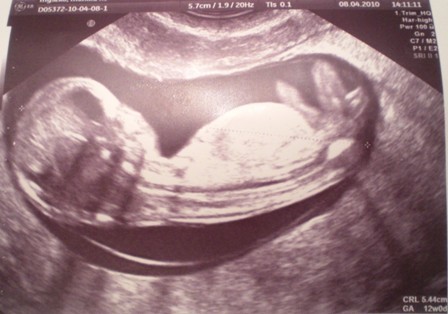

a oto moja slodycz- 12 tc

• 12tc..JPG

12tc..JPG

62,8 KB · Wyświetleń: 122